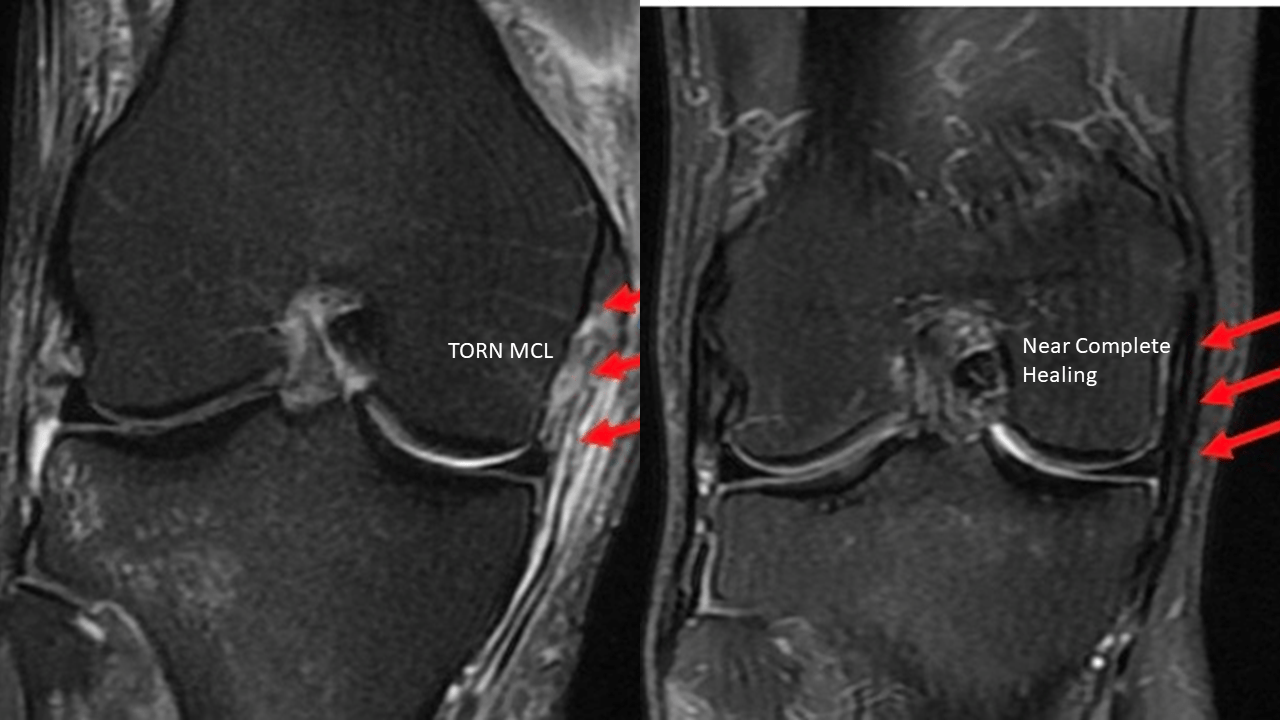

Medial Collateral Ligament (MCL) and Medial Supporting Structures

From radiologykey.com

Medial Collateral Ligament (MCL) and Medial Supporting Structures Old Mcl Injury Radiology Other signs include a wavy form of. Reference is made to the movement of the tibia with respect to the femur during stress testing. (minor sprain) high signal is seen medial. The most obvious sign of medial collateral ligament injury is its discontinuity in case of a partial or complete tear. In one specimen, the tibial portion of the mcl. Old Mcl Injury Radiology.